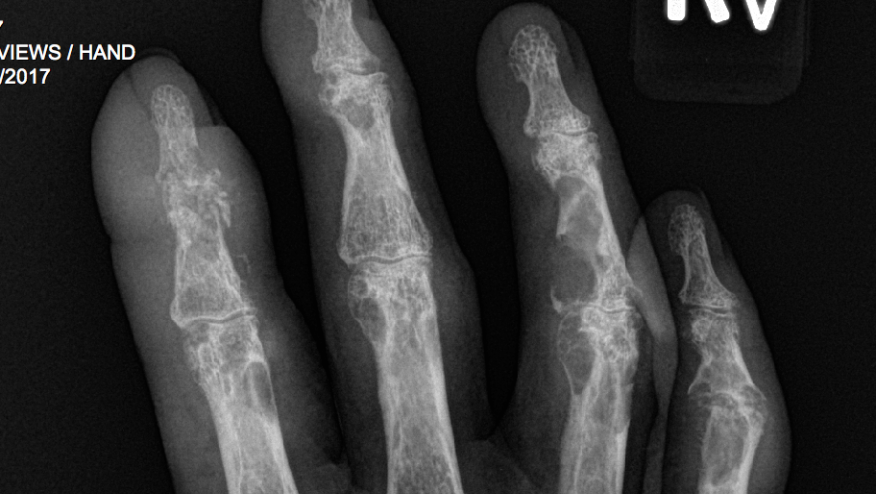

- If you have gout and type II diabetes you have worse gout. More tophi and erosions. Abstract #1118

- Double contour sign - earliest sign of uric acid deposition obs in asymptomatic gout pts. Abstract #250 http://ow.ly/YZtb30fDVzZ